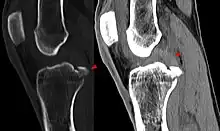

Procédés d'imagerie

Le diagnostic peut être confirmé par imagerie (IRM). Mais il faut noter que l'interprétation de l'IRM seule pour le diagnostic de rupture de LC conduit à 20 % de faux diagnostics. Cela dépend des images de coupe et de la position appropriée du genou pendant l'IRM. Le radiologue doit connaître avec précision les circonstances qui ont conduit à la blessure, et avoir aussi une bonne expérience de l'étude d'une articulation blessée, pour éviter les faux diagnostics. Pour comparer avec l'IRM, le taux d'erreur du test de Lachman, bien plus simple à accomplir, n'est que de 10 %[106],[107],[108],[109]. L'IRM est donc généralement moins sensible et moins spécifique que l'examen clinique par un orthopédiste qualifié[110]. Le résultat de l'IRM n'a que relativement rarement une influence sur la formulation finale du diagnostic[111] et ne devrait pas servir de remplacement pour une anamnèse soigneuse et la palpation[112]. Plusieurs études arrivent à la conclusion que l'IRM n'a de sens que pour des blessures complexes difficiles à expliquer, et là, pour éviter de poser un diagnostic négatif[113],[114],[115].

Les radios n'apportent aucune contribution immédiate au diagnostic de rupture de LC. Les deux LC sont invisibles à la radio, déchirés ou non. La seule utilité de la radio ne peut servir qu'au diagnostic des complications osseuses possibles.

Arthroscopie diagnostique

La sécurité diagnostique la meilleure est obtenue par arthroscopie diagnostique. Ce procédé représente l'étalon-or pour le diagnostic de la rupture de LC. Ce procédé relève d'une chirurgie invasive au minimum, mais comporte certains risques, comme toute intervention chirurgicale dans le genou du patient[116]. Comme cependant le traitement chirurgical d'une rupture de LC sera conduit par chirurgie arthroscopique, il est possible d'enchaîner celle-ci immédiatement après l'arthroscopie diagnostique, par la résection partielle du ligament (pour une déchirure) ou la reconstruction en cas d'arrachement. Avec l'accroissement de la facilité de l'IRM, le nombre d'arthroscopies purement diagnostiques a nettement diminué ces dernières années[117],[118]. L'arthroscopie diagnostique est quand même utilisée comme précédemment comme procédé de choix pour une compréhension certaine du diagnostic de rupture de LC, en cas d'examen clinique confus et d'IRM difficile à interpréter[116].